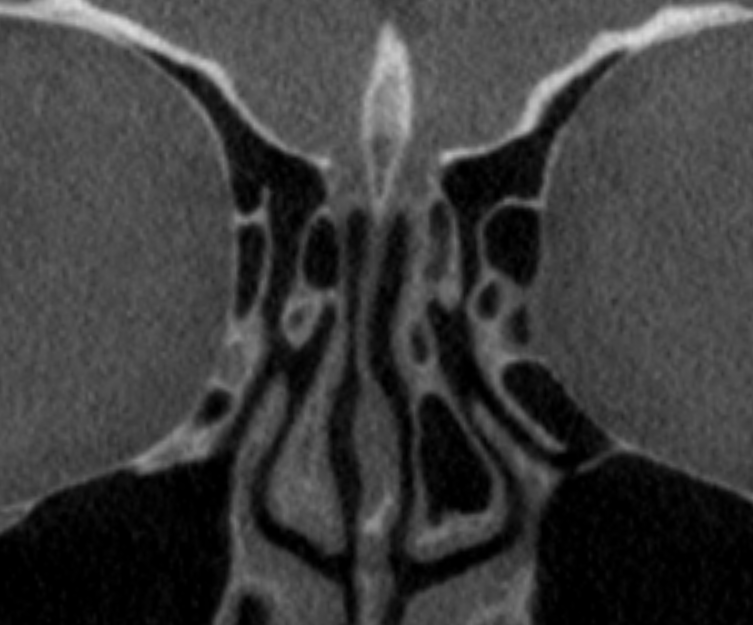

- Promover a compreensão detalhada da anatomia do nariz e seios paranasais, essencial para a realização de procedimentos cirúrgicos precisos e seguros.

- Dissecção em Peças Anatómicas Frescas: Uma das características distintas do nosso curso é a oportunidade de realizar dissecções em peças anatómicas frescas. Esta experiência prática essencial permite que os alunos explorem e compreendam a complexidade da anatomia nasal sob o ponto de vista cirúrgico, sob a orientação de nossos instrutores experientes.